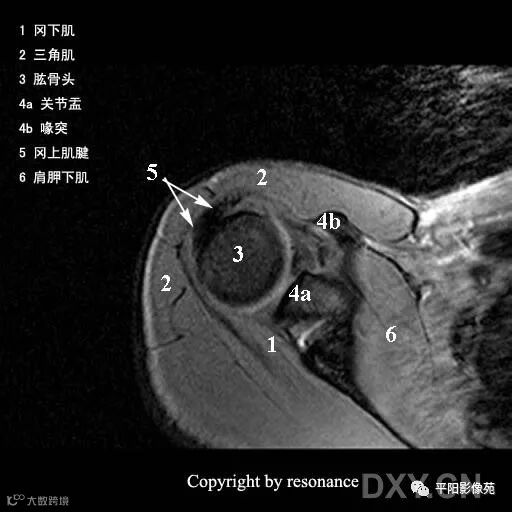

解剖

冈上肌肌腱:斜冠位、轴位显示最佳

止点位于肱骨大结节的上外侧面

冈下肌肌腱:轴位显示佳

止点位于肱骨大结节的后下方

小圆肌肌腱:轴位显示佳

指点位于肱骨大结节更下方,冈下肌肌腱下方

肩胛下肌肌腱:轴位和斜矢状位显示佳

止点位于肱骨小结节的前部